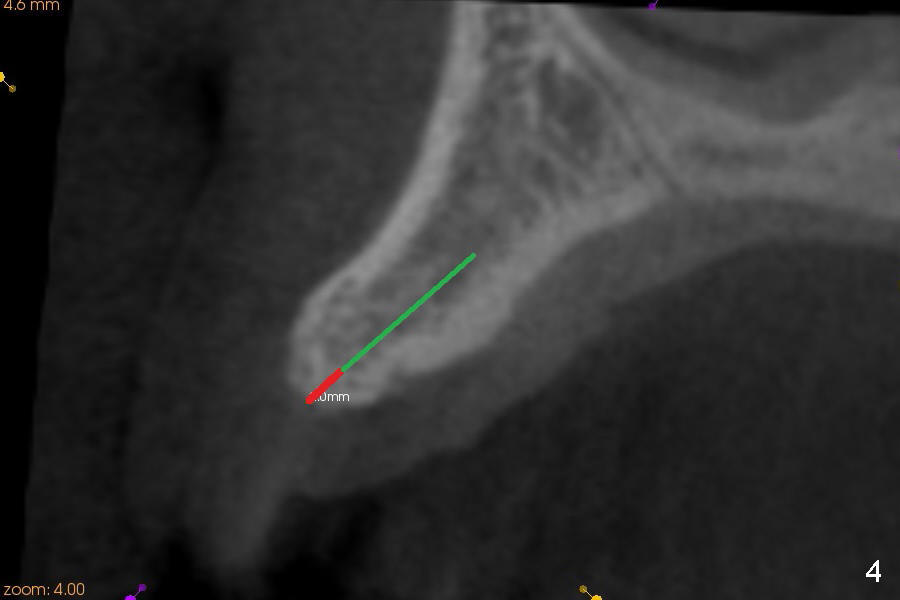

A 45-year-old lady has history of chronic periodontitis. The tooth #6 has lost several years (Fig.1). The buccolingual width decreases (Fig.2 (7mm), as compared to #11 in Fig.6 (10 mm)). Bone expansion is necessary for implantation. It should be done gently, since she is a dental phobic. First the crestal cortex is split with a surgical fissural bur (Fig.3 red line), followed by thin osteotomes (Fig.4 green line: scalpel, bone scalpels (probably until 5 or 6 mm, as indicated by Fig.1 (mesiodistal width)), bone blades (until 5.5 mm)). If the patient cannot tolerate tapping, 1.6 mm pilot drill is used at the depth of 14 mm, followed by bone expanders (probably until 2.9/3.8 using handpiece). As expanders or rounded osteotomes increases in diameter (Fig.5 green arrow), the buccal plate moves buccally (pink arrow). The bone expansion improves cosmetics as well. The implant is planned to be 4.5x14 mm, bone level. Angled abutment is expected. In contrast, immediate implant prevents buccal plate atrophy and avoids bone expansion. How is the surgery?